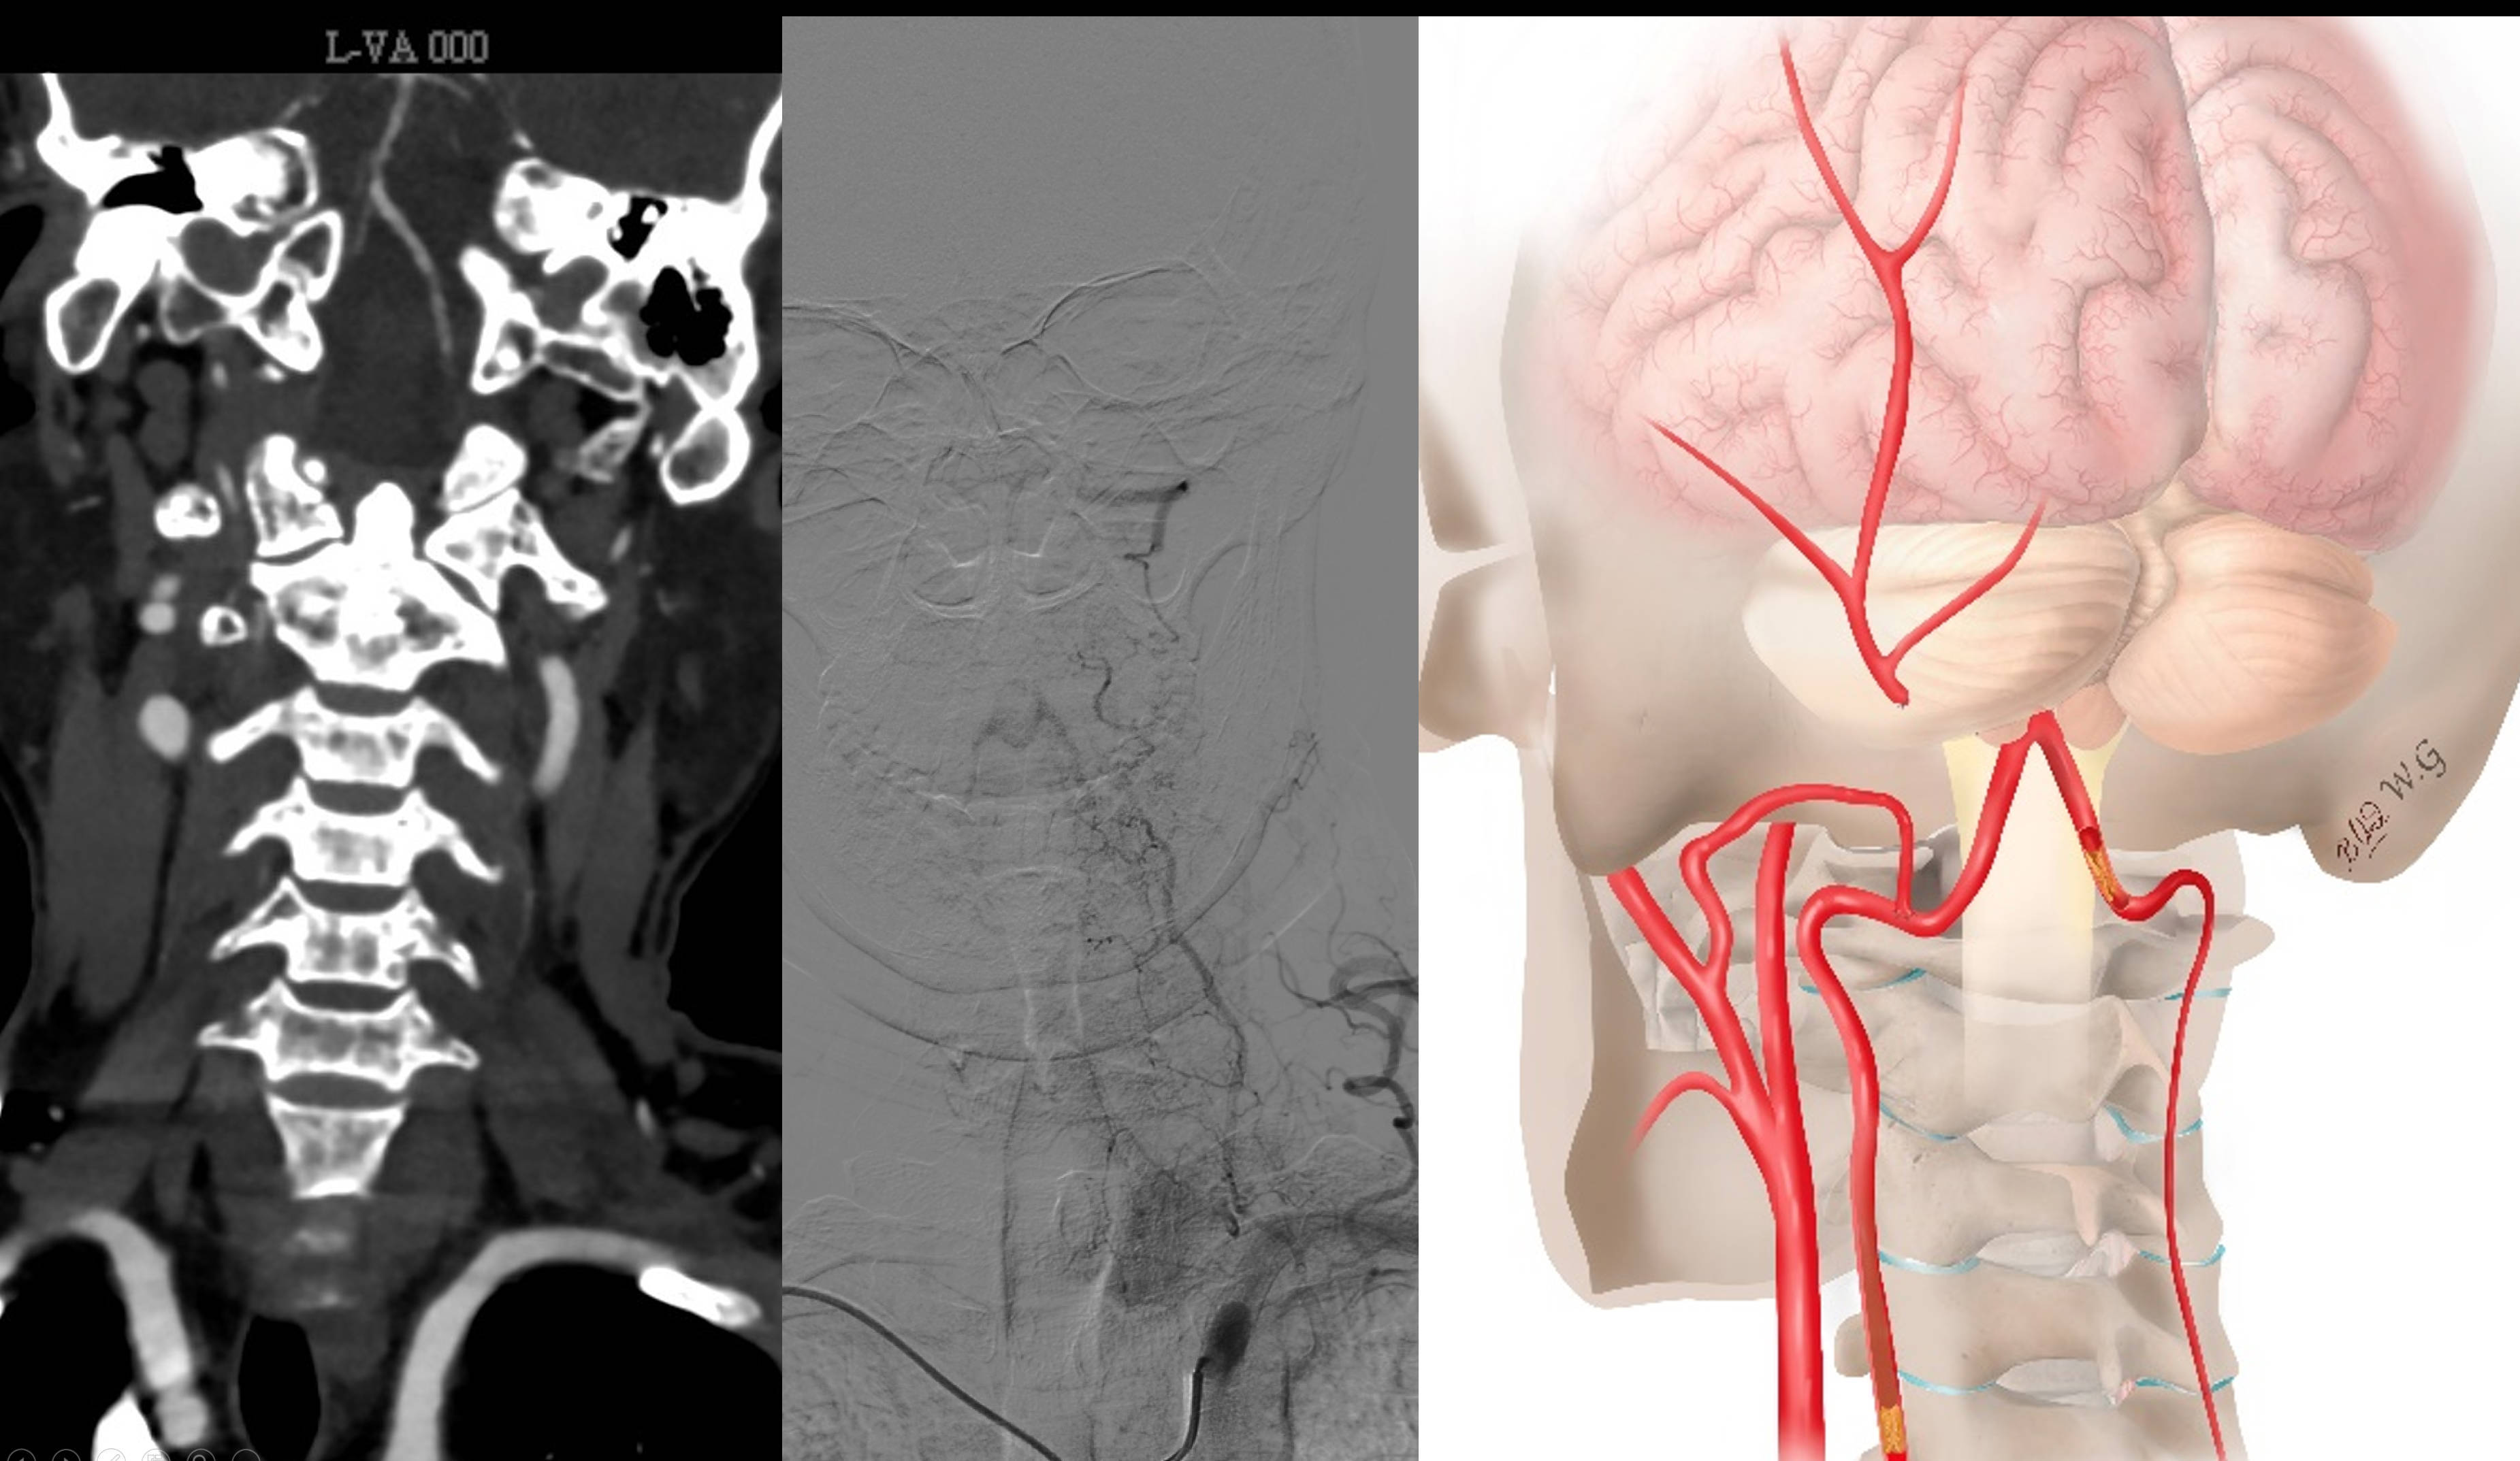

MRA提示左侧椎动脉闭塞,右侧发育不良,颅内段重度狭窄。

DSA造影看到左侧椎动脉V3段通过颈深动脉的肌支吻合代偿供血,但显影一般。

右侧椎动脉非优势,颅内段发育不良。

外院曾尝试开通,因起始部完全闭塞,不成功!

入院后的CTA确认闭塞,右侧VA发育不良!